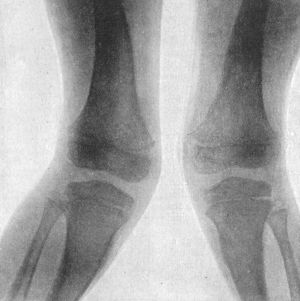

135.Genu Valgum and Genu Varum265

138.Radiogram of Case of Double Genu Valgum in a Child268

139.Genu Valgum in a Child. Patient standing269

140.Genu Valgum. Same Patient as Fig. 139, sitting270